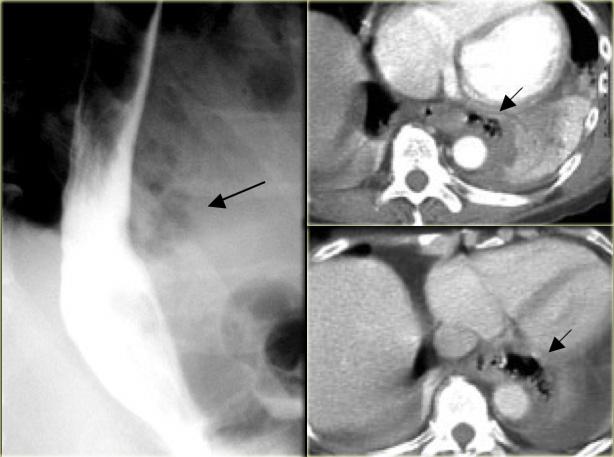

Bên trái là hình ảnh một bệnh nhân bị tụ máu thực quản.

Bệnh nhân nhập viện với triệu chứng đau ngực và khó nuốt sau khi nôn mửa.

Ngoài hình ảnh động mạch chủ ngoằn ngoèo, X-quang ngực bình thường.

Chụp thực quản barium cho thấy lòng thực quản hẹp (các mũi tên) trên phim thẳng và lòng thực quản dẹt trên phim nghiêng (các đầu mũi tên), gợi ý tụ máu trong thành thực quản.

Trên CT, chẩn đoán tụ máu trong thành thực quản được xác nhận.

Khối tụ máu thành thực quản tăng tỷ trọng (đầu mũi tên) được thấy cạnh ống thông mũi – dạ dày (mũi tên).

Sau điều trị bảo tồn, sáu tháng sau chụp thực quản barium cho kết quả bình thường.

Bên trái là hình ảnh một bệnh nhân có biến chứng sau nội soi phức tạp.

Can thiệp dụng cụ gây rách niêm mạc và tụ máu trong thành thực quản dạng bóc tách, tạo ra hình ảnh lòng đôi với dải niêm mạc phân tách (các mũi tên).

Ngoài cùng bên trái là hình ảnh thoát thuốc cản quang trong thành thực quản (mũi tên) sau nong đoạn xa điều trị co thắt tâm vị.

Ở giữa là hình ảnh thoát thuốc cản quang trong thành thực quản (mũi tên) sau nội soi phức tạp.

Bên phải là hình ảnh thủng thực quản sau sinh thiết với thuốc cản quang thoát ra ngoài lòng thực quản (mũi tên).